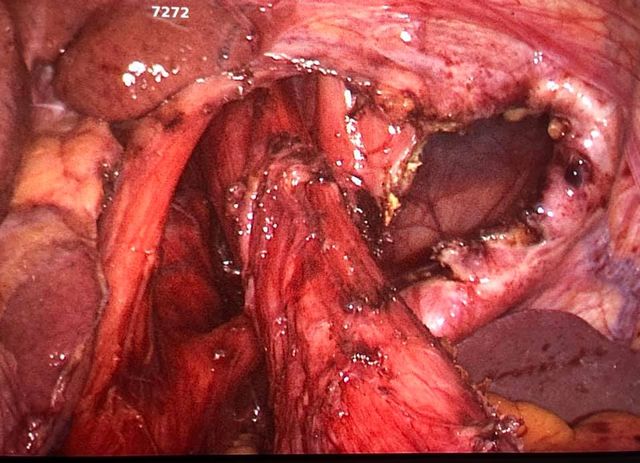

Challenging emergency during the COVID: Child’s A CLD with HUGE gastric varices uncontrolled

Child’s A CLD with HUGE gastric varices uncontrolled by Endoscopic glue and attempted EUS coiling. One salvage option would be TIPSS with balloon vascular occlusion but due to logistics we went for modified sugiura procedure. Splenectomy + Gastro esophageal devascularisation with anterior Gastrotomy and overseeing of gastric varices with pyloroplasty. Images show 1 CECT showing large gastric fundal varices. 2,3,4 Gastro Esophageal devasc 5, 6 Large fundal varices before and after oversewing. 7. Anterior gastrotomy 8. Pyloroplasty. Postoperative recovery was uneventful.